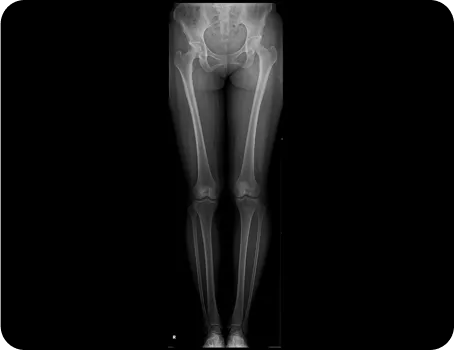

풀스파인 촬영으로

신체의 전체적인 문제를 파악하고

통증의 정확한 원인을 찾아

재발을 예방하고, 통증을 개선하는

치료를 합니다.

머리부터 발끝까지 완벽하게 체형을 분석 후

통증을 만들어낸 가해자가 누군지를 찾아내서 치료합니다.